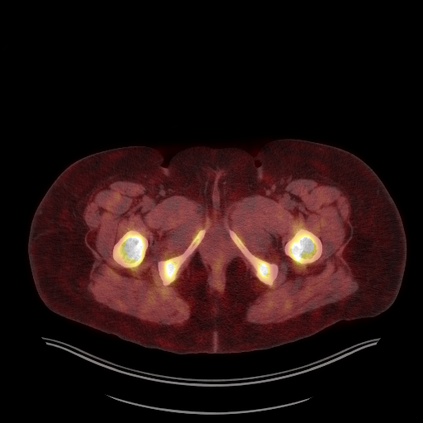

Medical images play a crucial role in assisting diagnosis, remote consultation, and academic research. However, during the transmission and sharing process, they face serious risks of copyright ownership and content tampering. Therefore, protecting medical images is of great importance. As an effective means of image copyright protection, zero-watermarking technology focuses on constructing watermarks without modifying the original carrier by extracting its stable features, which provides an ideal approach for protecting medical images. This paper aims to propose a fragile zero-watermarking model based on dual quaternion matrix decomposition, which utilizes the operational relationship between the standard part and the dual part of dual quaternions to correlate the original carrier image with the watermark image, and generates zero-watermarking information based on the characteristics of dual quaternion matrix decomposition, ultimately achieving copyright protection and content tampering detection for medical images.